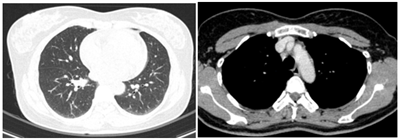

Case lâm sàng: Ứng dụng trí tuệ nhân tạo (Artificial intelligence – AI) trong chẩn đoán và điều trị sớm Ung thư phổi tại Trung tâm Y học hạt nhân và... Ngày đăng: 17/01/2026 Theo GLOBOCAN 2022, ung thư phổi đứng đầu về số ca mới mắc (2.480.301 ca mới mắc chiểm 12.4%) và dẫn đầu số ca tử vong (1.817.172 ca tử vong chiếm 18.7%) trên toàn thế giới. Tại Việt Nam tỷ lệ mắc...